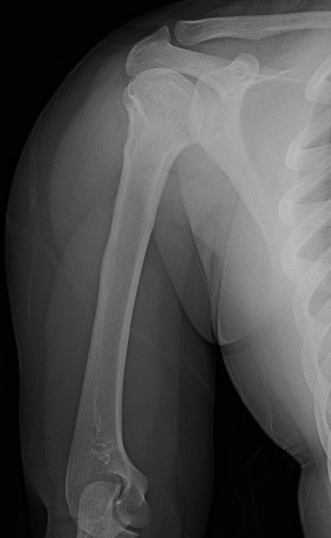

多数可采用非手术治疗:大多数10岁以下儿童因生长潜力充足,即使严重移位骨折也可通过塑形自行矫正

五,保守治疗

可接受的复位标准:

-

<5岁:成角≤70度,可接受100%移位

5-11岁:成角40-70度,移位50%-100%

>12岁:成角<40度,移位<50%